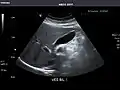

Kidneys: Right and left kidneys measure 11.5 cm and 12 cm in length respectively. No hydronephrosis. Small left lower pole kidney cyst.

Left kidney -